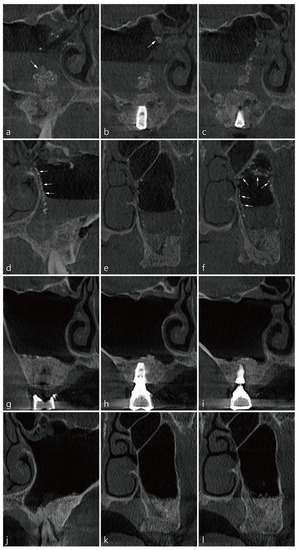

4. Case 2

5. Case 3

6. Case 4